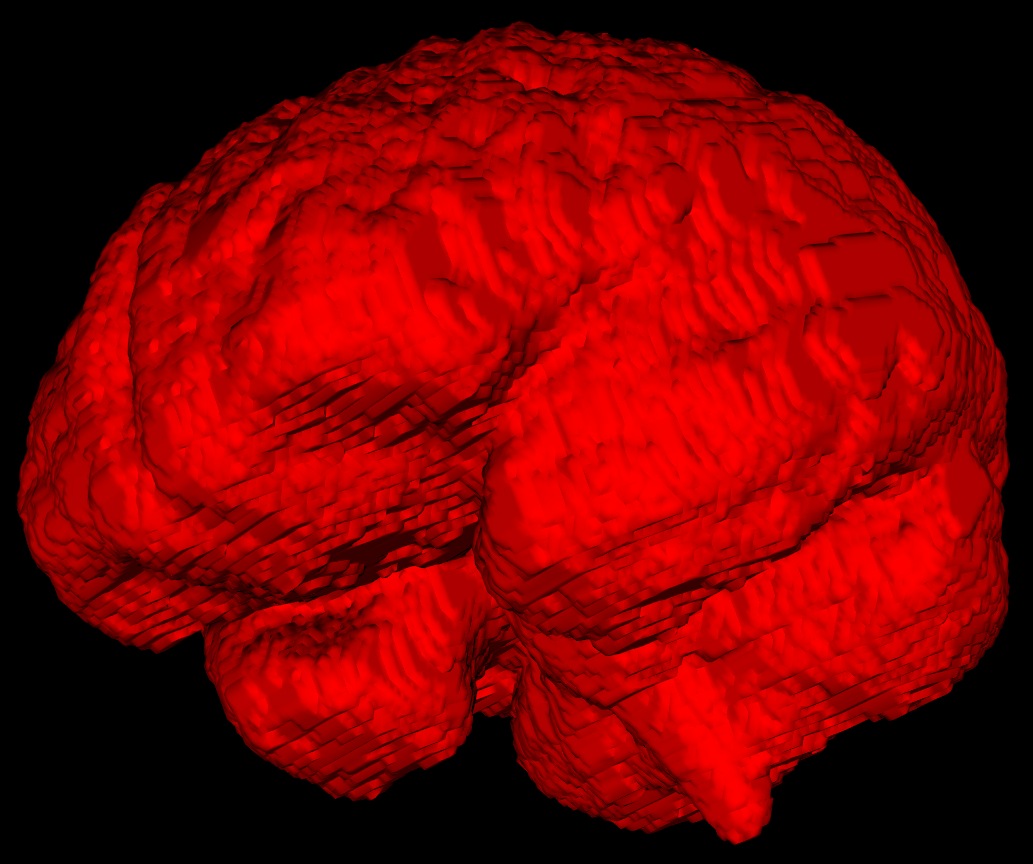

Synthetic training

Due to the nature of medical imaging, there is a limit to supervised training possible

Thus, deep learning models learning crucial anatomical information from limited examples

Simulating anatomical structures to create synthetic images have been recently proposed as an alternative.

As a way of populating a small or non-existent dataset, it has proven to increase generalizability drastically, with even higher accuracy in some cases